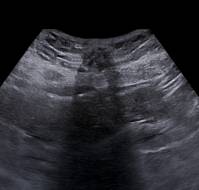

The presence of an echogenic mass on ultrasound is the most sensitive and specific sonographic indicator of retained products of conception (RPOC) following any p..